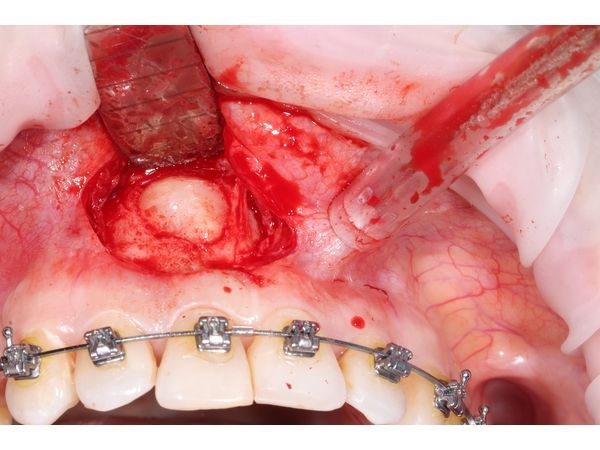

- создали окно для доступа к верхушке корня с помощью бормашины;

- пинцетом аккуратно извлекли кисту вместе с оболочкой и остатками пломбировочного материала за верхушкой корня;